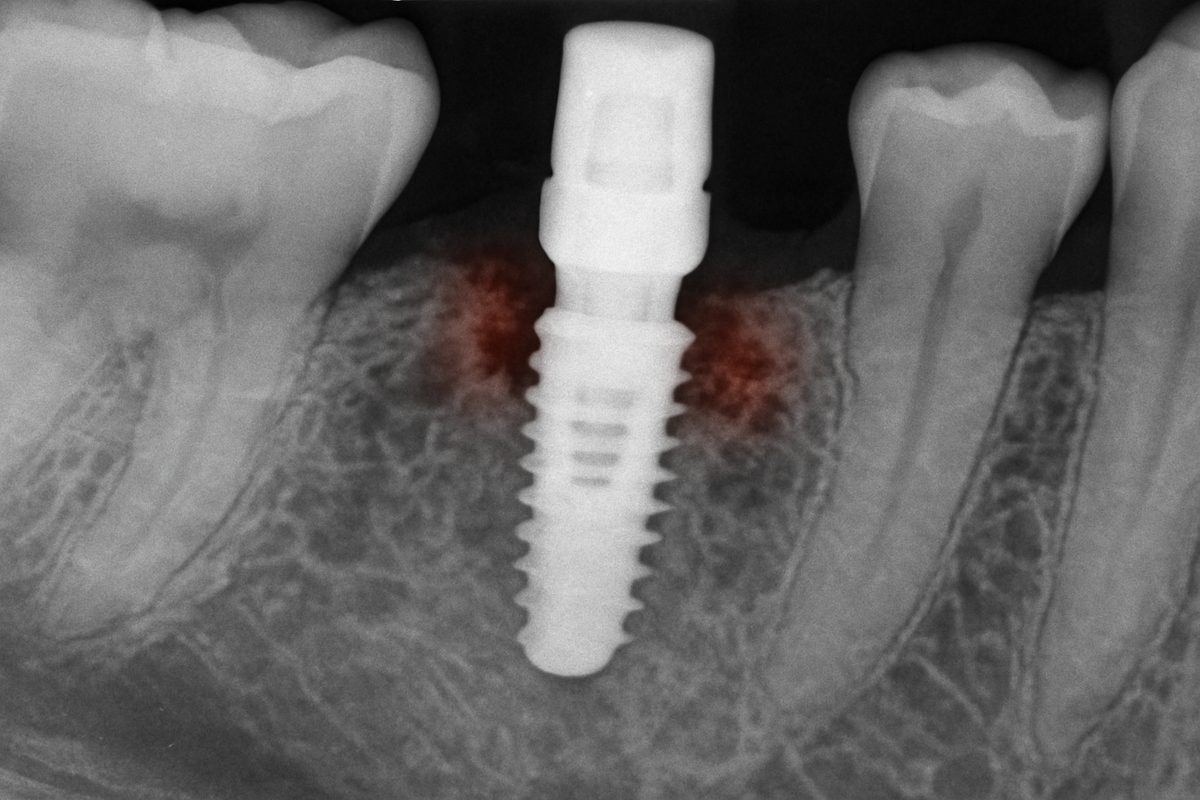

Peri-implantitis (infection and inflammation)

Peri-implantitis is infection around the implant that causes swelling, bleeding, and bone loss. Left untreated, it can lead to implant failure.

An implant that feels mobile may not have integrated with bone or may have lost support from bone resorption. Early detection improves chances of saving the implant.